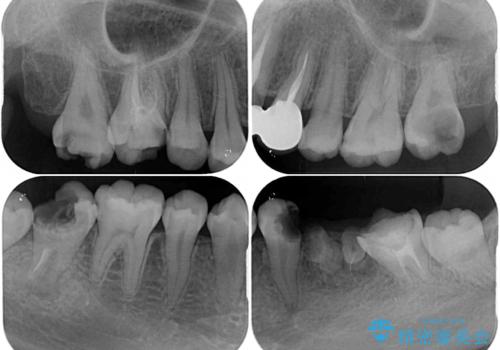

痛みのある歯が多く、根管治療が必要と診断されました。

左下の歯は、クラウンを装着するために必要な高さが足りないため、歯冠長を延長するための外科処置を行うこととしました。

根管治療や歯周外科処置後にフルジルコニアクラウンにて補綴治療することとしました。